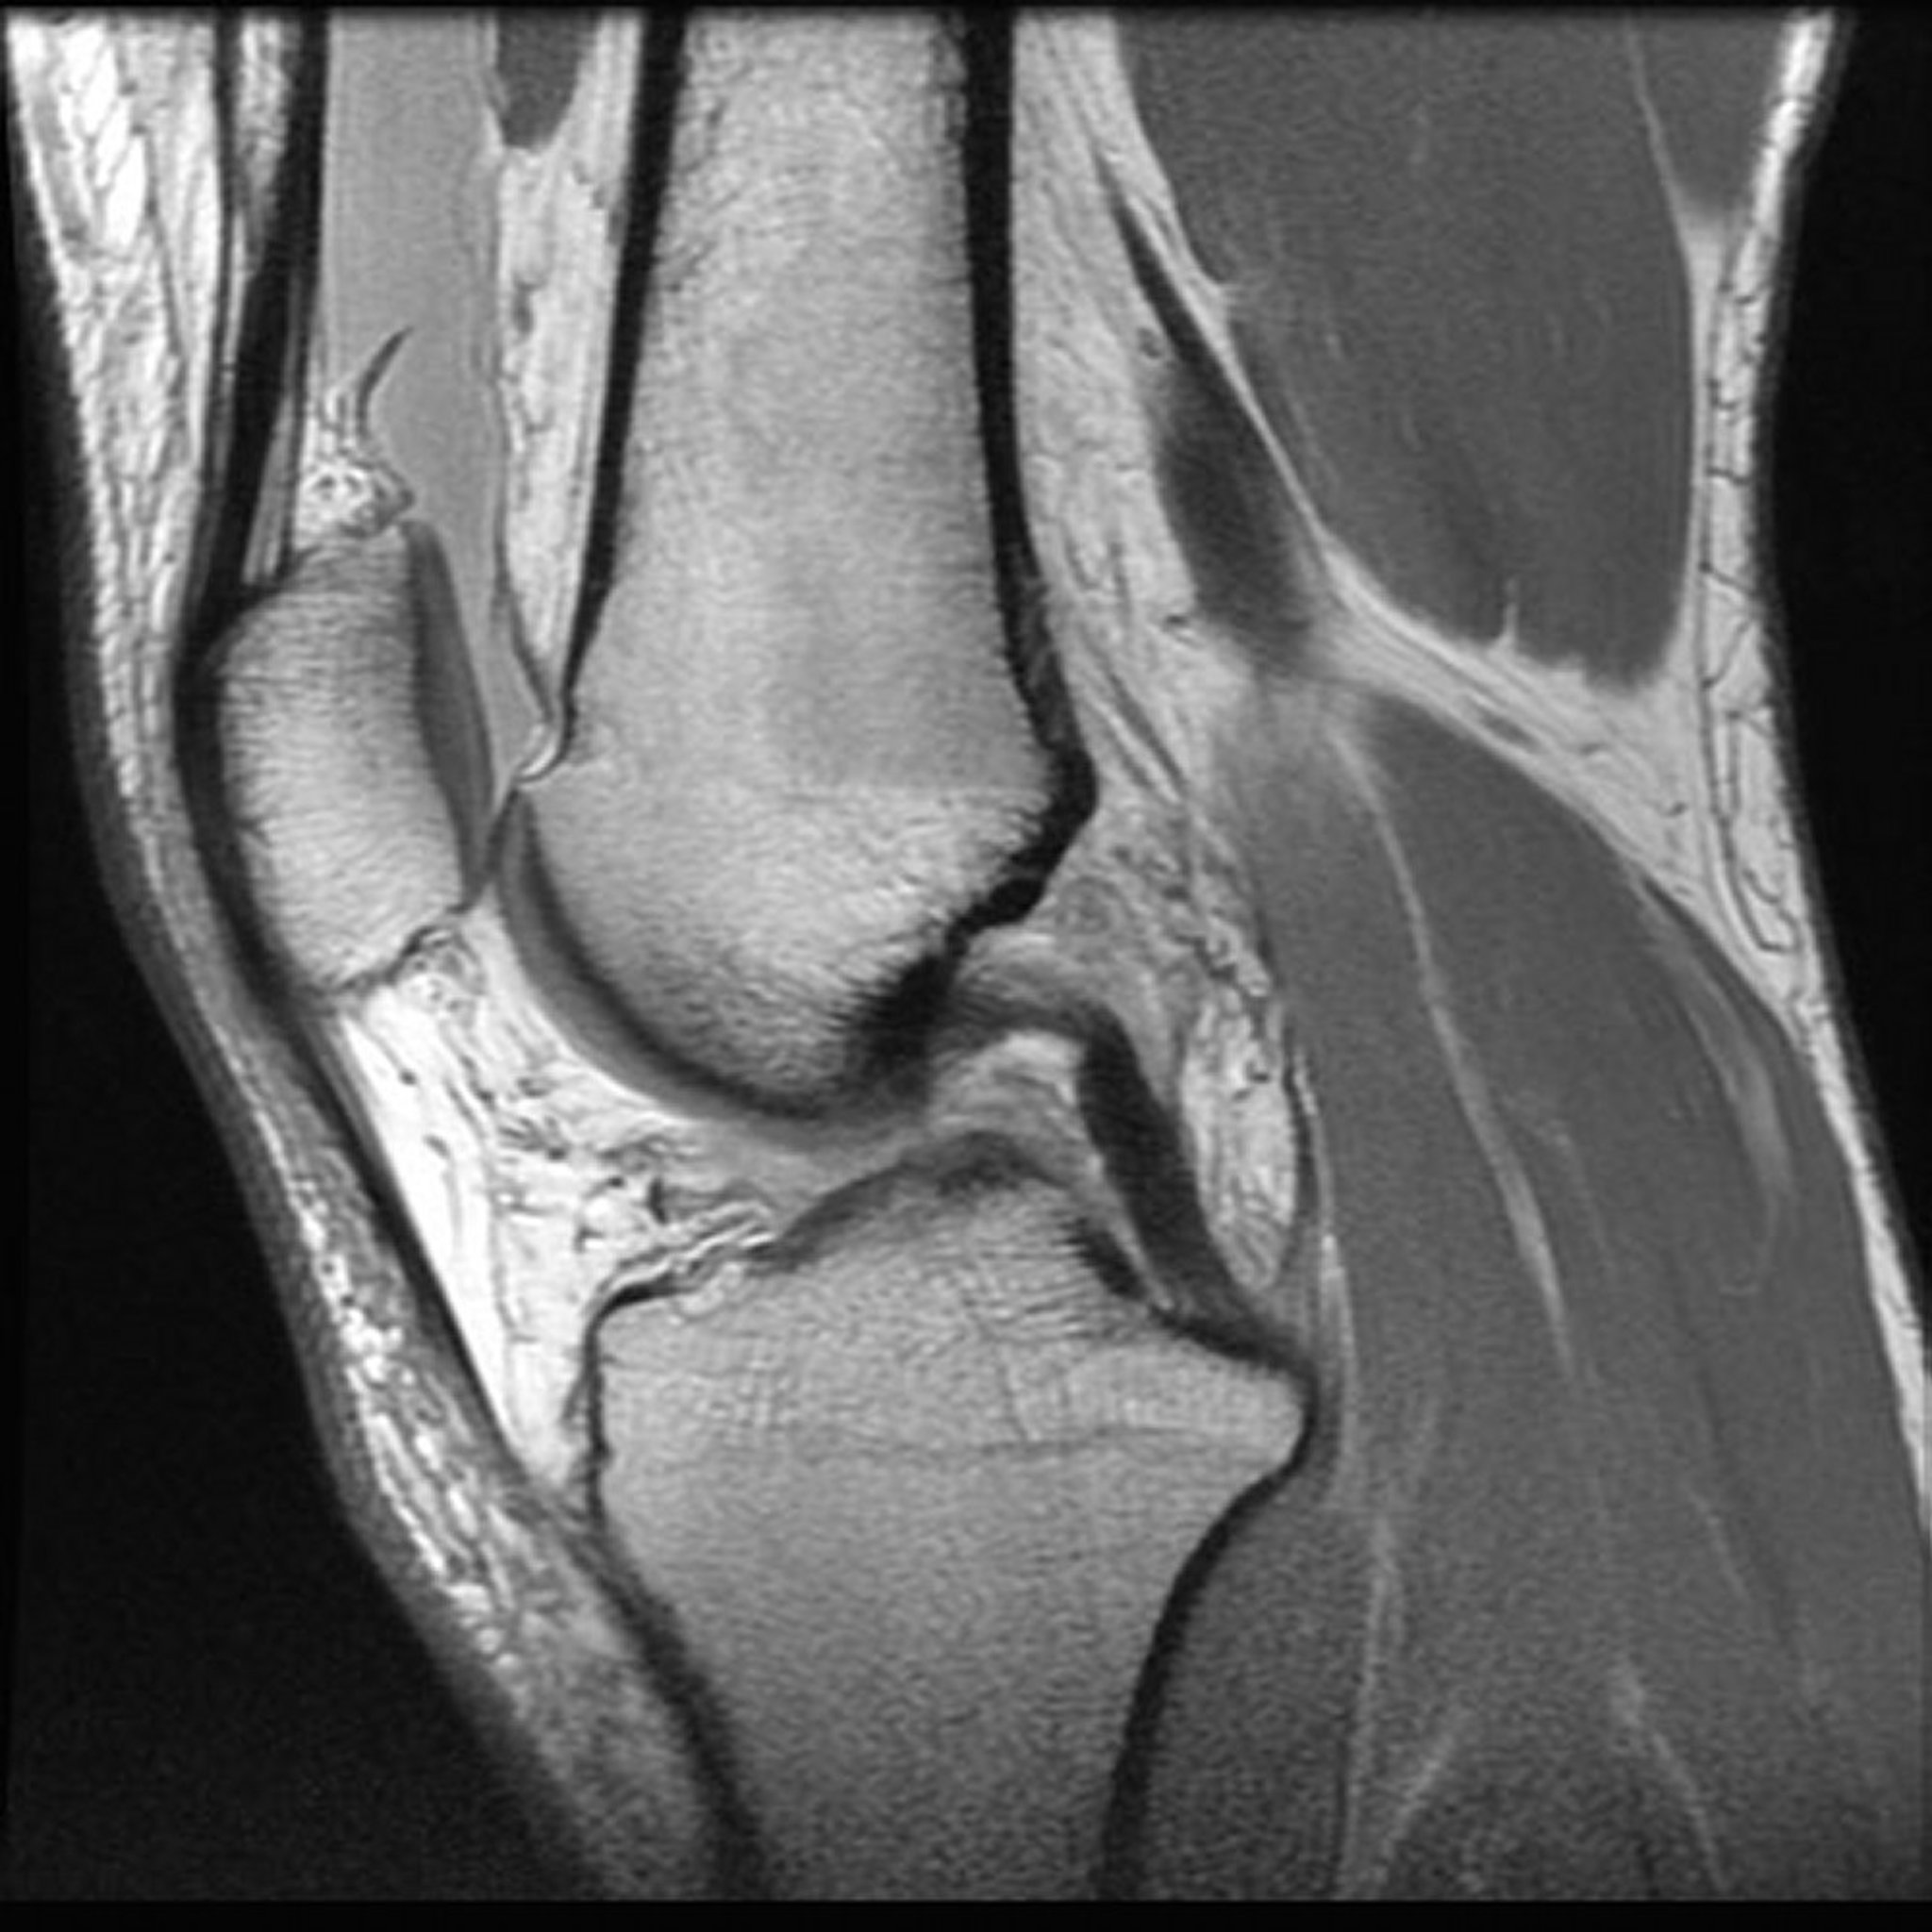

Magnetic Resonance Imaging (MRI) of the Knee

Image provided by Jon A Jacobson, MD.